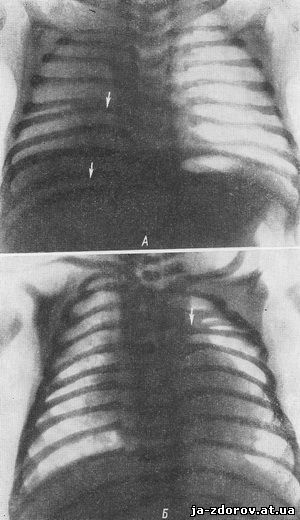

Медицина и диагностика: Аномалии ребер на рентгене